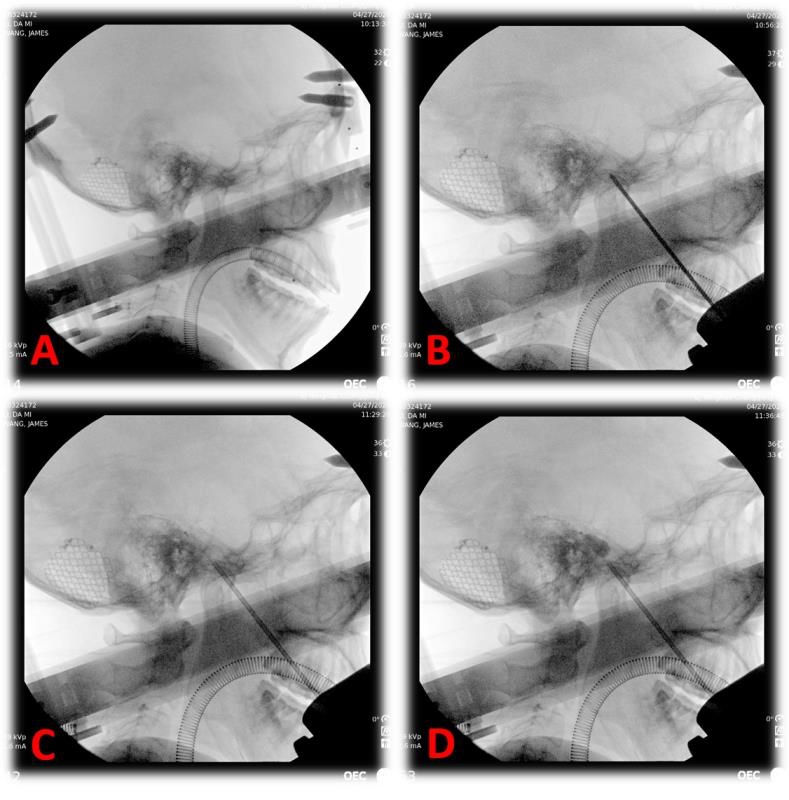

图为术中X光片提示穿刺位置准确

这种技术是用微创经皮穿刺的方法,在颅底一个叫迈克尔腔的地方打起一个花生米大小的小水球,机械压迫损毁三叉神经节和部分神经根以达到止痛目的。这种方法创伤小、安全可靠、恢复快、花费少。但手术需要精确定位,手术最大的挑战是要把穿刺针穿入10公分外的卵圆孔,大约有衬衫扣子1/4的大小。大多医院限于条件,都是在X线、C形臂、CT引导下徒手进行。

图为术中穿刺成功后向球囊内注入造影剂

北京清华长庚医院运用机器人手术,其精度可达到亚毫米级,准确度更高,保证了一针入孔,实际术中仅用10秒钟即完成了穿刺操作,避免了重要血管、脑组织的损伤,而且减少了术中X线的照射,大大减少了患者的手术风险。同时,考虑到患者的美观和舒适,神经外科住院总医师董生将Leksell头架改装后连接手术机器人。这结合了立体定向技术和机器人技术,化繁为简,省略了患者需要剃发和在头上固定骨性标志点的操作。